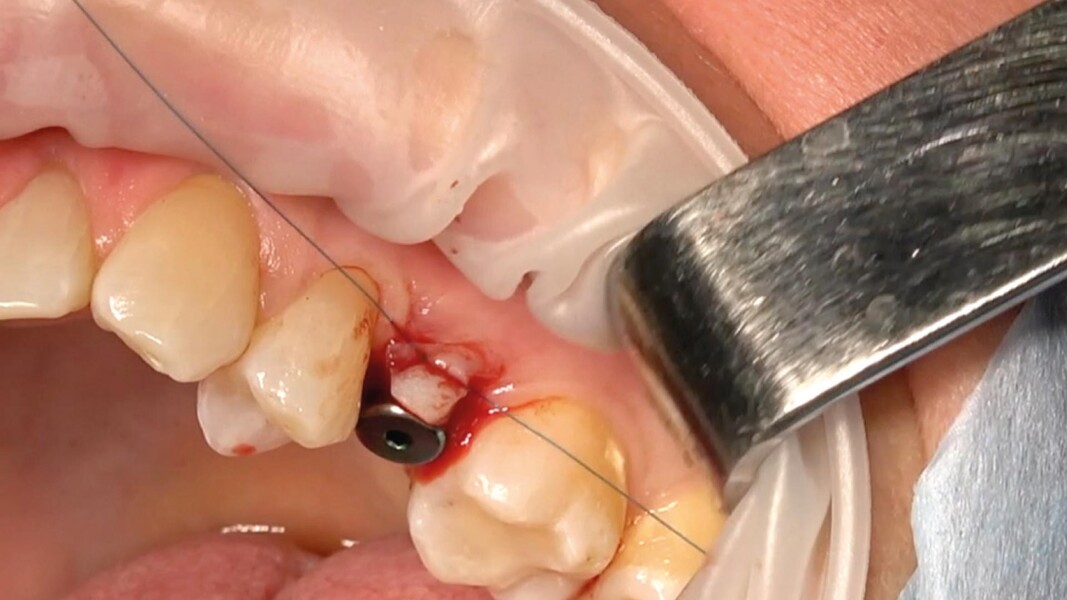

Una paziente di 50 anni presentava un premolare superiore non recuperabile. Dopo CBCT preoperatoria (T0) (Fig. 1), si è proceduto all’estrazione atraumatica e alla gestione dell’alveolo mediante posizionamento vestibolare di una membrana corticale eterologa (Lamina fine 0,7 mm, 35 × 15 mm, OsteoBiol) e riempimento con spugne di collagene (Figg. 2, 3). Sono stati applicati punti di sutura in nylon non riassorbibile 4/0. Dopo sei mesi di guarigione, una nuova CBCT (T1) ha consentito la valutazione della qualità ossea. Per la fase implantare è stato eseguito un lembo secondo la tecnica del roll flap, con preservazione delle papille interdentali e aumento del tessuto cheratinizzato (Fig. 4). È stato inserito un impianto JD Evolution Plus (4,3 × 11,5 mm) ottenendo un’eccellente stabilità primaria. Durante la chirurgia è stato prelevato un campione osseo per analisi istologica (Fig. 5).  Il lembo è stato suturato con nylon 4/0 intorno all’abutment di guarigione. Dopo due mesi, la paziente è stata riabilitata con una corona monolitica in zirconia realizzata da impronta digitale intraorale (Fig. 6).